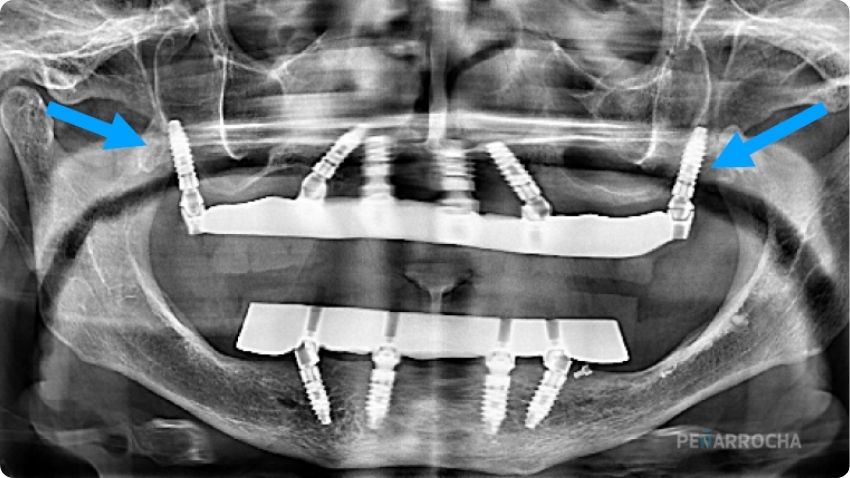

Los Dres. Miguel y David Peñarrocha, especialistas en implantología avanzada, han practicado con éxito la técnica de implantes pterigoideos en Valencia y la han documentado en múltiples publicaciones científicas. Su enfoque combina cirugía mínimamente invasiva con rehabilitación protésica inmediata. Sigue leyendo para conocer sus beneficios, indicaciones y si es adecuada para ti.

Un implante pterigoideo se coloca en la parte posterior del maxilar superior, anclado al hueso pterigoideo. Esta zona ofrece una densidad ósea alta y permite fijar una prótesis completa sin necesidad de injertos ni elevaciones de seno.

La técnica se emplea como alternativa a los injertos óseos y a los implantes cigomáticos, permitiendo restauraciones fijas incluso cuando hay atrofia severa en el maxilar tipo V o VI.